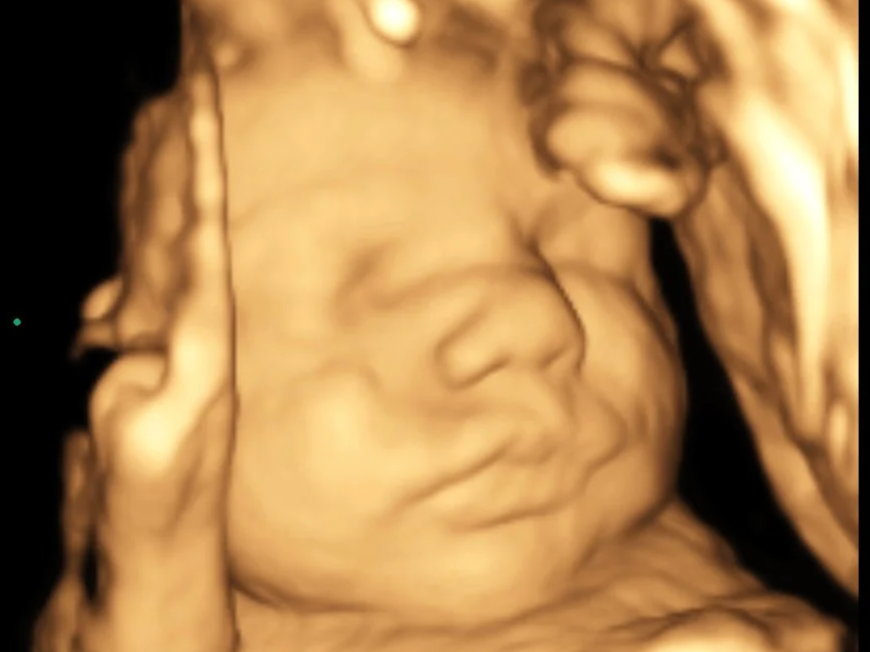

8K Ultrasound Images A Premium Upgrade to Your 3D Baby Ultrasound Our work speaks for itself — Our work speaks for itself — Our work speaks for itself —